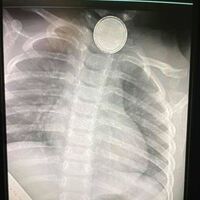

Las cápsulas de detergente son uno de los productos de limpieza que más intoxicaciones causan en niños

NoticiasEntre 2016 y 2020 se produjeron en Estados Unidos más de 20.000 lesiones relacionadas con la ingesta accidental de cápsulas de detergente entre los menores de 18 años. Así lo advierte una investigación publicada en el Journal of Dental...